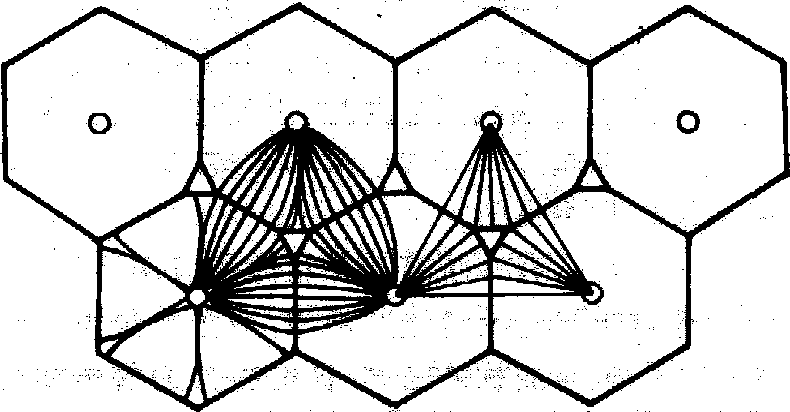

哺乳动物肝的构造 肝表面大部分被覆浆膜,湿润而光滑,其深面为致密结缔组织构成的被膜,在肝门处结缔组织增多并随血管和肝管分支入肝,构成肝的支架。根据肝的结构和功能特点,曾提出经典肝小叶(六边形)、门管小叶(三角形)、和肝腺泡(椭圆形)三种肝单位的概念(图1)。

图 1 三种肝单位示意图

门管小叶 以门管区为中轴画出的小叶结构,大致为三角形的柱状体。横切面呈三角形,柱状体的长轴与肝小叶的长轴一致,轴心为门管,周围以三个中央静脉的连线为界。肝细胞分泌的胆汁从小叶周边向中轴汇集进入小叶间胆管,因此门管小叶着重强调肝的外分泌功能。

肝腺泡 肝腺泡的最小单位是单腺泡,略呈卵圆形,中轴为门管的终末分支,两端以中央静脉为界。相邻的两个单腺泡,其肝板和窦状隙相互连续,无任何界限。每个单腺泡内肝细胞分泌的胆汁,通过胆小管经中轴处的终末胆管输出,中轴处的终末血管分支则将营养物质和代谢产物输入单腺泡内。肝腺泡是肝的结构和功能单位的较新概念,着重强调肝细胞与血液供给之间的关系,因而有利于说明肝细胞结构功能上的梯度差异,以及肝的病理变化和肝细胞的再生等问题。